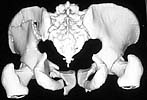

On admission patient was hypotensive. Evaluation revealed him to be having an unstable pelvic ring injury, D12 vertebral body fracture, free fluid in the abdomen and a suspected urinary bladder injury. After his haemodynamic status was better he was taken up for an emergency laparotomy (midline approach). Though there was free blood stained fluid in the peritoneum no hollow viscus injury or other organ damage was noted. Urinary bladder contusion present but no tear. At he same sitting the anterior pelvic ring was stabilised using reconstruction plates through an extended Pfannensteil approach. After a couple of days the posterior ring was stabilised using reconstruction plates (posterior approach). The spine was not interfered surgically since this was inherently stable and there were no neurological findings. The posterior wound grumbled for some time and settled down. He was kept in bed but allowed free turning in bed.

The X rays and few CT reconstructions attached. Kindly give your valuable comments. What all would have been better ways of management?

The iliac fracture with associated sacroiliac anterior disruption (some call this a "crescent fracture-dislocation") might allow manipulative reduction and percutaneous iliosacral screw fixation....it's difficult to know if an iliosacral screw would work without a routine 2-D CT to examine. It might not be possible for this specific fracture because of it's location. The screw must connect the unstable iliac component to the sacrum...some have used iliosacral screws for these "more anterior" iliac fracture patterns, but the iliosacral screw is mistakenly inserted through the stable iliac posterior (crescent fragment) component into the sacrum...that screw doesn't accomplish much....don't do that!